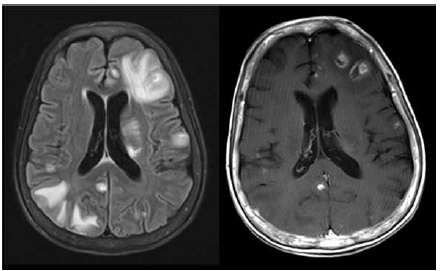

Paciente do sexo masculino, 48 anos, com quadro de confusão mental há 7 dias. Tem antecedente de HIV há 18 anos, com interrupção do tratamento por conta própria há 3 anos. Ao exame, está desorientado e desatento. Realizou a ressonância magnética de crânio mostrada a seguir. O líquor tem 7 células (linfomononuclear) com bioquímica normal e tinta da China negativa.

A principal hipótese diagnóstica é: